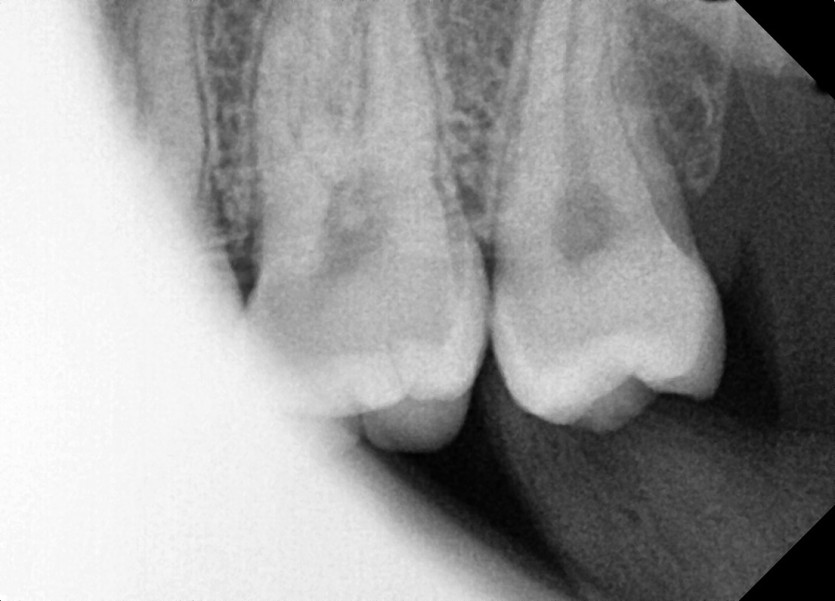

#28,38 사랑니 발치

구강외과 전문의가 당일 발치했습니다.